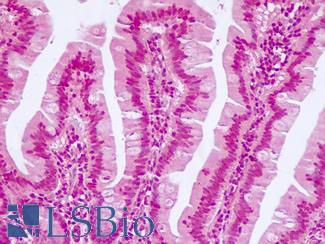

CK20 (KRT20)

Anti-KRT20 / Cytokeratin 20 antibody IHC staining of human small intestine. Immunohistochemistry of formalin-fixed, paraffin-embedded tissue after heat-induced antigen retrieval. Antibody LS-B10488 dilution 1:200.

CK20 (KRT20)

Anti-KRT20 / Cytokeratin 20 antibody IHC of human small intestine. Immunohistochemistry of formalin-fixed, paraffin-embedded tissue after heat-induced antigen retrieval. Antibody LS-B5959 dilution 1:50. This image was taken for the unconjugated form of this product. Other forms have not been tested.